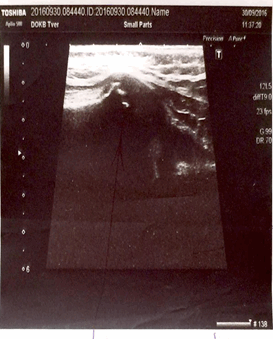

Ультразвуковая диагностика проводилась всем пациентам с МЭО (n=97; 100%), в дебюте заболевания выполнена у 29 детей (29,89%). Методика высоковерифицируема во время операции. Чувствительность метода - 92,5%, специфичность - 84,6%, точность - 91,04%. Определялись следующие эхографические признаки: увеличение толщины мягкотканых структур, скопление жидкости вокруг сустава, со стороны полости сустава наблюдались утолщение капсулы, присутствие внутрисуставной жидкости; изменения структуры эпифизарного хряща, формы и структуры ядра, окостенения эпифиза, изменения эхогенности зоны метаэпифиза, размытость ее границ, гиперэхогенность надкостницы и ее утолщение, нарушение границ наружного контура. Изменения в метаэпифизарной зоне - основной эхографический признак МЭО - регистрировались на 4-7-й день болезни. У пациентов в интрамедуллярной фазе обнаружены: отек параоссальных мягких тканей (n=15; 51%), утолщение капсулы сустава (n=10; 34%), жидкость в полости сустава (n=11; 37%). В экстрамедуллярной фазе на 4-7-й день МЭО: изменения эпифизарного хряща в виде участков повышенной эхогенности (n=31; 64%), нечеткость контура метафиза (n=35, 72%), утолщение надкостницы (n=26; 51%) (рис. 2).

Рис. 2. Сонограммы левой бедренной кости. УЗ-картина деструктивного процесса